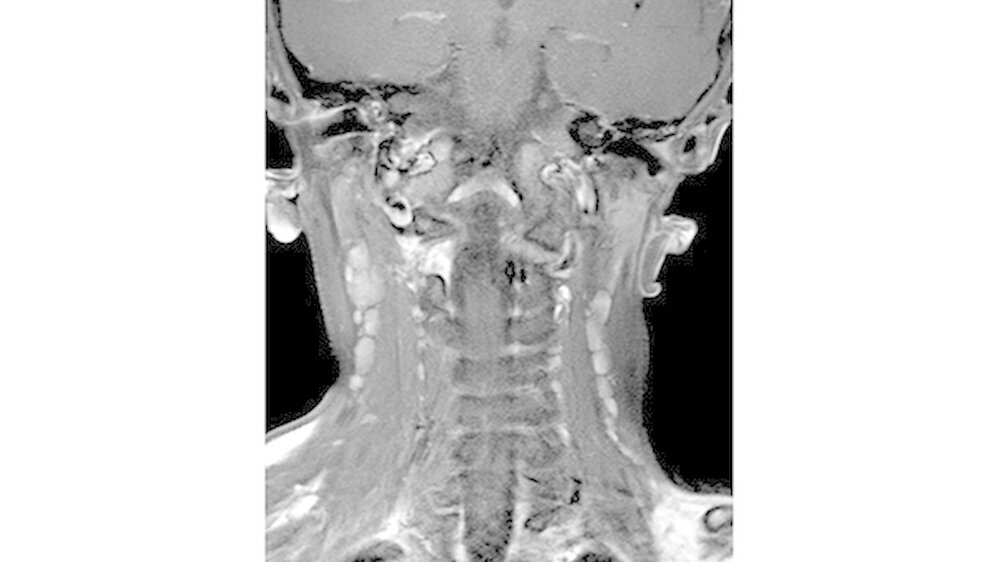

Sonografisch fielen multiple pathologisch vergrößerte Lymphknoten am Hals beidseits auf. Dies bestätigte sich in der MRT, welche darüber hinaus eine Infiltration von Ober- und Unterkiefer, Schläfen- und Keilbein mit ossärer Destruktion und Knochen überschreitender Weichteilkomponente aufwies (Abbildung 4). Weitere Herde wurden im Schulterblatt, am Humerus-Kopf, sowie im Schlüsselbein, und an den Halswirbeln festgestellt.